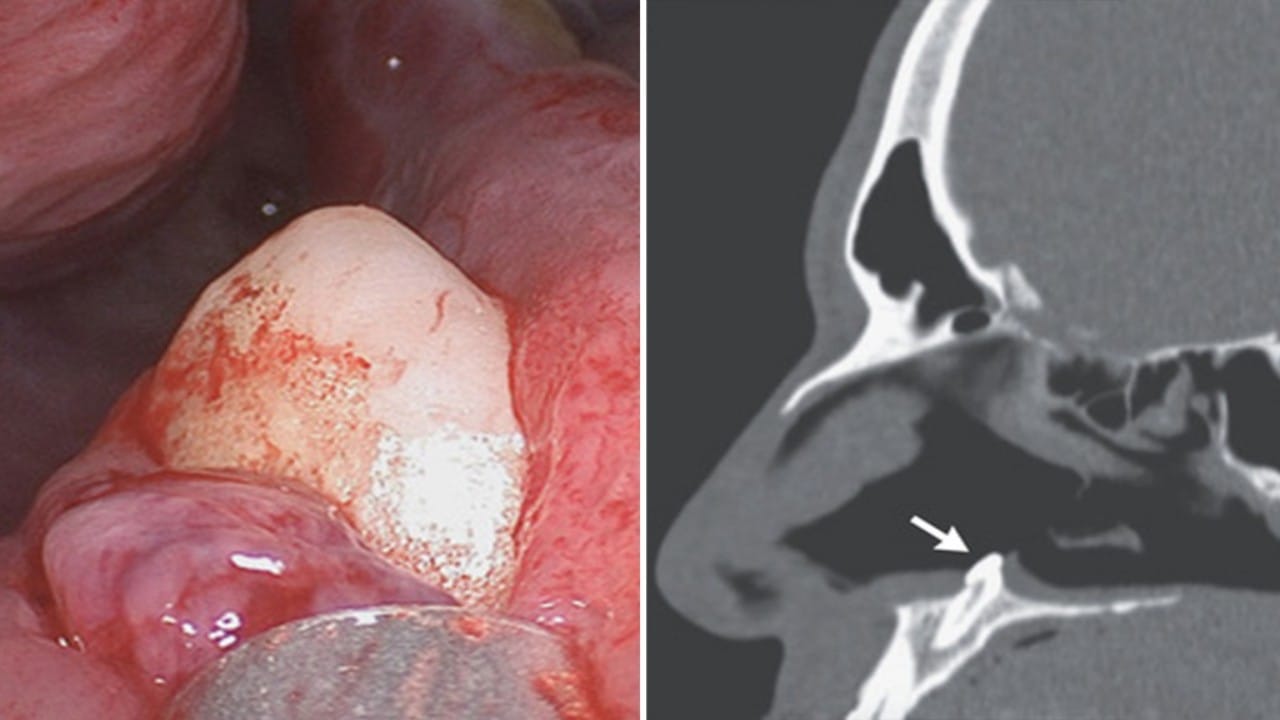

رجل يعاني من صعوبة التنفس بسبب نمو سن داخل أنفه

خلع سن في أنف سيدة صينية